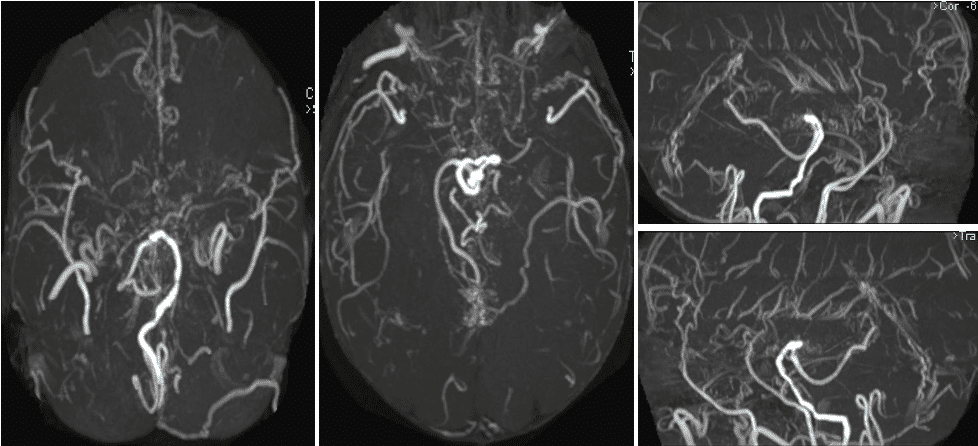

头MRA提示双侧大脑前、大脑中及左侧大脑后动脉显影不清,颅内大量烟雾血管生成;